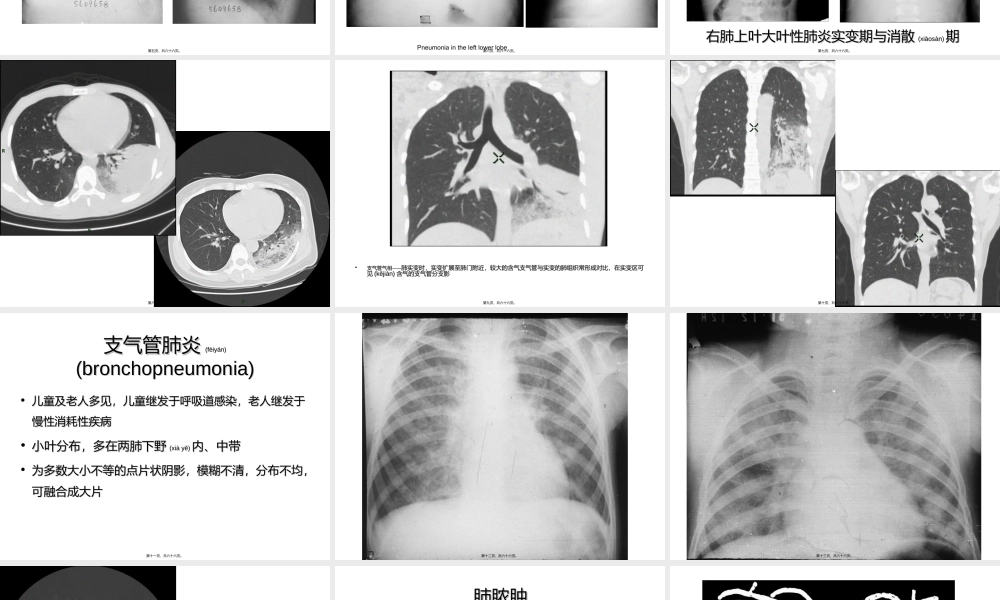

呼吸系统呼吸系统(hūxīxìtǒnɡ)(hūxīxìtǒnɡ)影像学影像学•北京大学第一医院北京大学第一医院•医学影像科医学影像科第一页,共六十六页。肺炎肺炎(fèiyán)(fèiyán)pneumoniapneumonia•病因病因::感染性:细菌性、病毒性、支原体感染性:细菌性、病毒性、支原体过敏性过敏性物理和化学因素物理和化学因素•部位部位(bùwèi)(bùwèi)::大叶性肺炎大叶性肺炎lobarpneumonialobarpneumonia支气管肺炎支气管肺炎bronchopeumoniabronchopeumonia第二页,共六十六页。大叶性肺炎大叶性肺炎(lobarpneumonia)(lobarpneumonia)•肺炎双球菌,青壮年,铁锈色痰肺炎双球菌,青壮年,铁锈色痰•早期无明显改变,或仅有肺纹理增加,进而出早期无明显改变,或仅有肺纹理增加,进而出现较淡的模糊影现较淡的模糊影•肝样变期,大叶实变,密度均匀,范围和肺叶轮廓肝样变期,大叶实变,密度均匀,范围和肺叶轮廓相同相同,,可有可有支气管气相支气管气相。。•病变吸收,阴影逐渐消散,但比临床病变吸收,阴影逐渐消散,但比临床(línchuánɡ)(línchuánɡ)症状症状消退晚消退晚•节段性肺炎更常见节段性肺炎更常见第三页,共六十六页。Pneumoniaintherightmiddlelobe第四页,共六十六页。第五页,共六十六页。Pneumoniaintheleftlowerlobe第六页,共六十六页。右肺上叶大叶性肺炎实变期与消散右肺上叶大叶性肺炎实变期与消散(xiāosàn)(xiāosàn)期期第七页,共六十六页。第八页,共六十六页。•支气管气相支气管气相————肺实变时,实变扩展至肺门附近,较大的含气支气管与实变的肺组织常形成对比,在实变区可肺实变时,实变扩展至肺门附近,较大的含气支气管与实变的肺组织常形成对比,在实变区可见见(kějiàn)(kějiàn)含气的支气管分支影含气的支气管分支影第九页,共六十六页。第十页,共六十六页。支气管肺炎支气管肺炎(fèiyán)(fèiyán)(bronchopneumonia)(bronchopneumonia)•儿童及老人多见,儿童继发于呼吸道感染,老人继发于儿童及老人多见,儿童继发于呼吸道感染,老人继发于慢性消耗性疾病慢性消耗性疾病•小叶分布,多在两肺下野小叶分布,多在两肺下野(xiàyě)(xiàyě)内、中带内、中带•为多数大小不等的点片状阴影,模糊不清,分布不均,为多数大小不等的点片状阴影,模糊不清,分布不均,可融合成大片可融合成大片第十一页,共六十六页。第十二页,共六十六页。第十三页,共六十六页。第十四页,共...